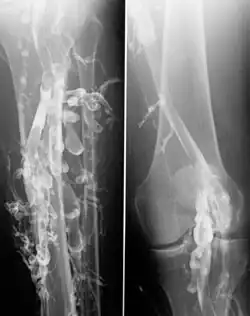

Flebografia (synonim wenografia) – badanie polegające na podaniu do żyły środka cieniującego (tzw. kontrastu), umożliwiającego uwidocznienie jej światła i zobrazowanie na zdjęciu rentgenowskim; może być również składową angiografii tomografii komputerowej (angio-TK) i jądrowego rezonansu magnetycznego (angio-MR).

- flebografię bezpośrednią, gdy środek cieniujący podawany jest bezpośrednio do układu żylnego. Jeżeli środek cieniujący wstrzykuje się do żyły i wędruje on zgodnie z kierunkiem przepływu krwi (na przykład kontrast wstrzykuje się do żył stopy, aby zakontrastować żyły kończyny dolnej) mówi się o flebografii bezpośredniej wstępującej. Jeżeli natomiast kontrast podaje się w kierunku przeciwnym do kierunku krążenia krwi (podanie kontrastu przez cewnik do żyły głównej dolnej aby uzyskać zakontrastowanie żył nerkowych), mówi się o flebografii bezpośredniej zstępującej.